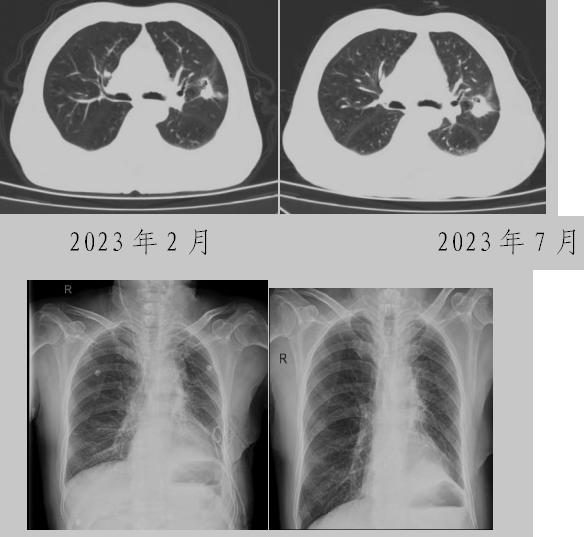

病例一:70多歲的患者王先生于2020年“急性心梗”入院時檢查發(fā)現了肺部結節(jié),王先生沒有在意,其間未規(guī)范復查胸部影像學檢查,于2023年2月份再次發(fā)作心絞痛時,發(fā)現肺結節(jié)已發(fā)展成直徑約2.5cm實性腫塊,患者在家長期口服“替格瑞洛及腸溶阿司匹林”等抗凝藥物,生活可自理,于冠狀動脈二次植入支架后三個月,收住市二院胸外科,經心內科、麻醉科等多學科會診后,由胸外科主任王松陽、副主任醫(yī)師薛飛及科室團隊行“單孔胸腔鏡下左上肺癌根治術”,術后結合快速康復理念,三天后拔除胸管,一周出院。